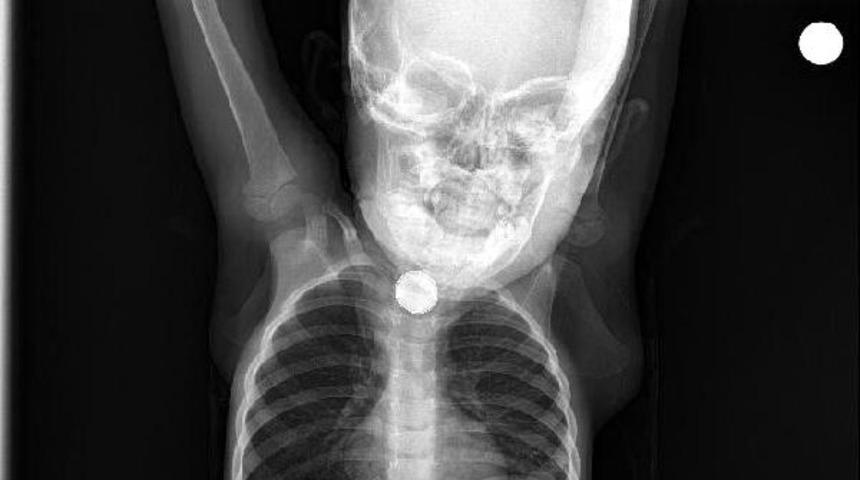

Burada yapılan kontrolde yassı pil yuttuğu tespit edilen Berfin, ameliyata alındı. Küçük kızın boğazının alt kısmındaki pil, başarılı operasyonla çıkarıldı. Ramazanoğlu çifti ise kızlarının, yaklaşık 3 ay önce yerde oynarken, bir cisim yuttuğunu hatırlayınca, pil yutmuş olabileceğini söyledi.

Operasyonu gerçekleştiren Tıp Fakültesi Çocuk Gastroenteroloji, Hepatoloji ve Beslenme Bilim Dalı Başkanı Prof. Dr. Yaşar Doğan, "Tanı amaçlı yaptığımız endoskopi neticesinde, Berfin’in, yassı bir pil yuttuğunu belirledik.

Pili çıkardıktan sonra uzun süre orada kalmasından dolayı yemek borusunda ciddi yanıklar meydana gelmişti. Hatta bu yanıklar nerdeyse nefes borusuyla birleşecek şekilde bir oluşuma gidecekti. Hastamız şu an sağlığına kavuştu. Kliniğimizde şu an oral beslenmeye geçildi. Yarın taburcu etmeyi düşünüyoruz. Yine takiplerimiz devam edecek" dedi.